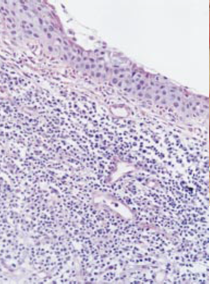

On histological examination (figure 2), samples of conjunctival and corneal specimens show a lymphocytic infiltration along with neutrophils, eosinophils, plasma cells, and mast cells [4],[18] . High levels of proteolytic enzymes have been found in affected conjunctival tissue [18]. When the limbal cornea is examined, it can show vascularization and infiltration of plasma cells and lymphocytes into the superficial stroma in addition to the destruction of the collagen matrix [4]. The midstroma may show disorganized collagen lamellae and hyperactive fibroblasts, while the deep stroma contains a macrophage infiltrate. The leading edge of the ulcer can show neutrophilic infiltration with evidence of degranulation. Adjacent conjunctiva may show a hyperplastic epithelium and subconjunctival lymphocytic and plasma cell infiltration [4]. It has also been shown that elevated NF-κB activity may be responsible for the pathology.[19]